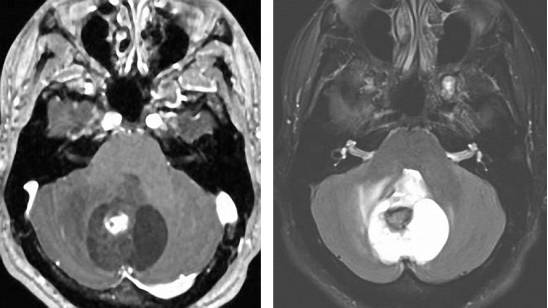

图5. 髓母细胞瘤在T1相上相对白质呈低信号,往往呈不均匀强化。在T2相上,由于钙化、坏死和囊性变的存在往往表现为混杂信号。